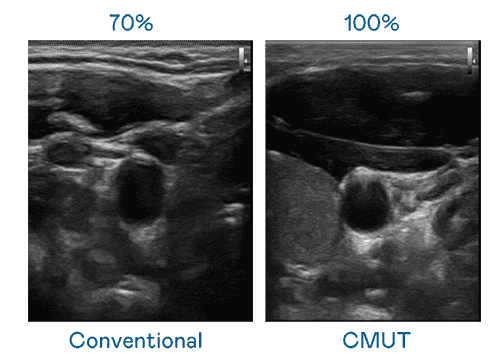

CMUT 技术是一种用电容式微机电元件来产生超音波讯号的技术。。。。与传统 PZT 压电式技术相比,,,CMUT 频宽增加 30%,,更宽频的超音波讯号让影像解析度大幅提升,,是实现高影像品质医疗超音波扫描、、促进精准医疗发展的关键技术。。

大频宽带来超清晰影像

超音波影像的解析度高低,,,,首先取决于探头能发出的讯号频宽。。。。OBPay CMUT 可提供高清晰的超音波讯号,,,提供高频宽、、、、高灵敏度、、、影像纹理细节更高的超音波影像,,协助医护人员缩短影像判读时间及利用精准的医疗影像进行诊断。。